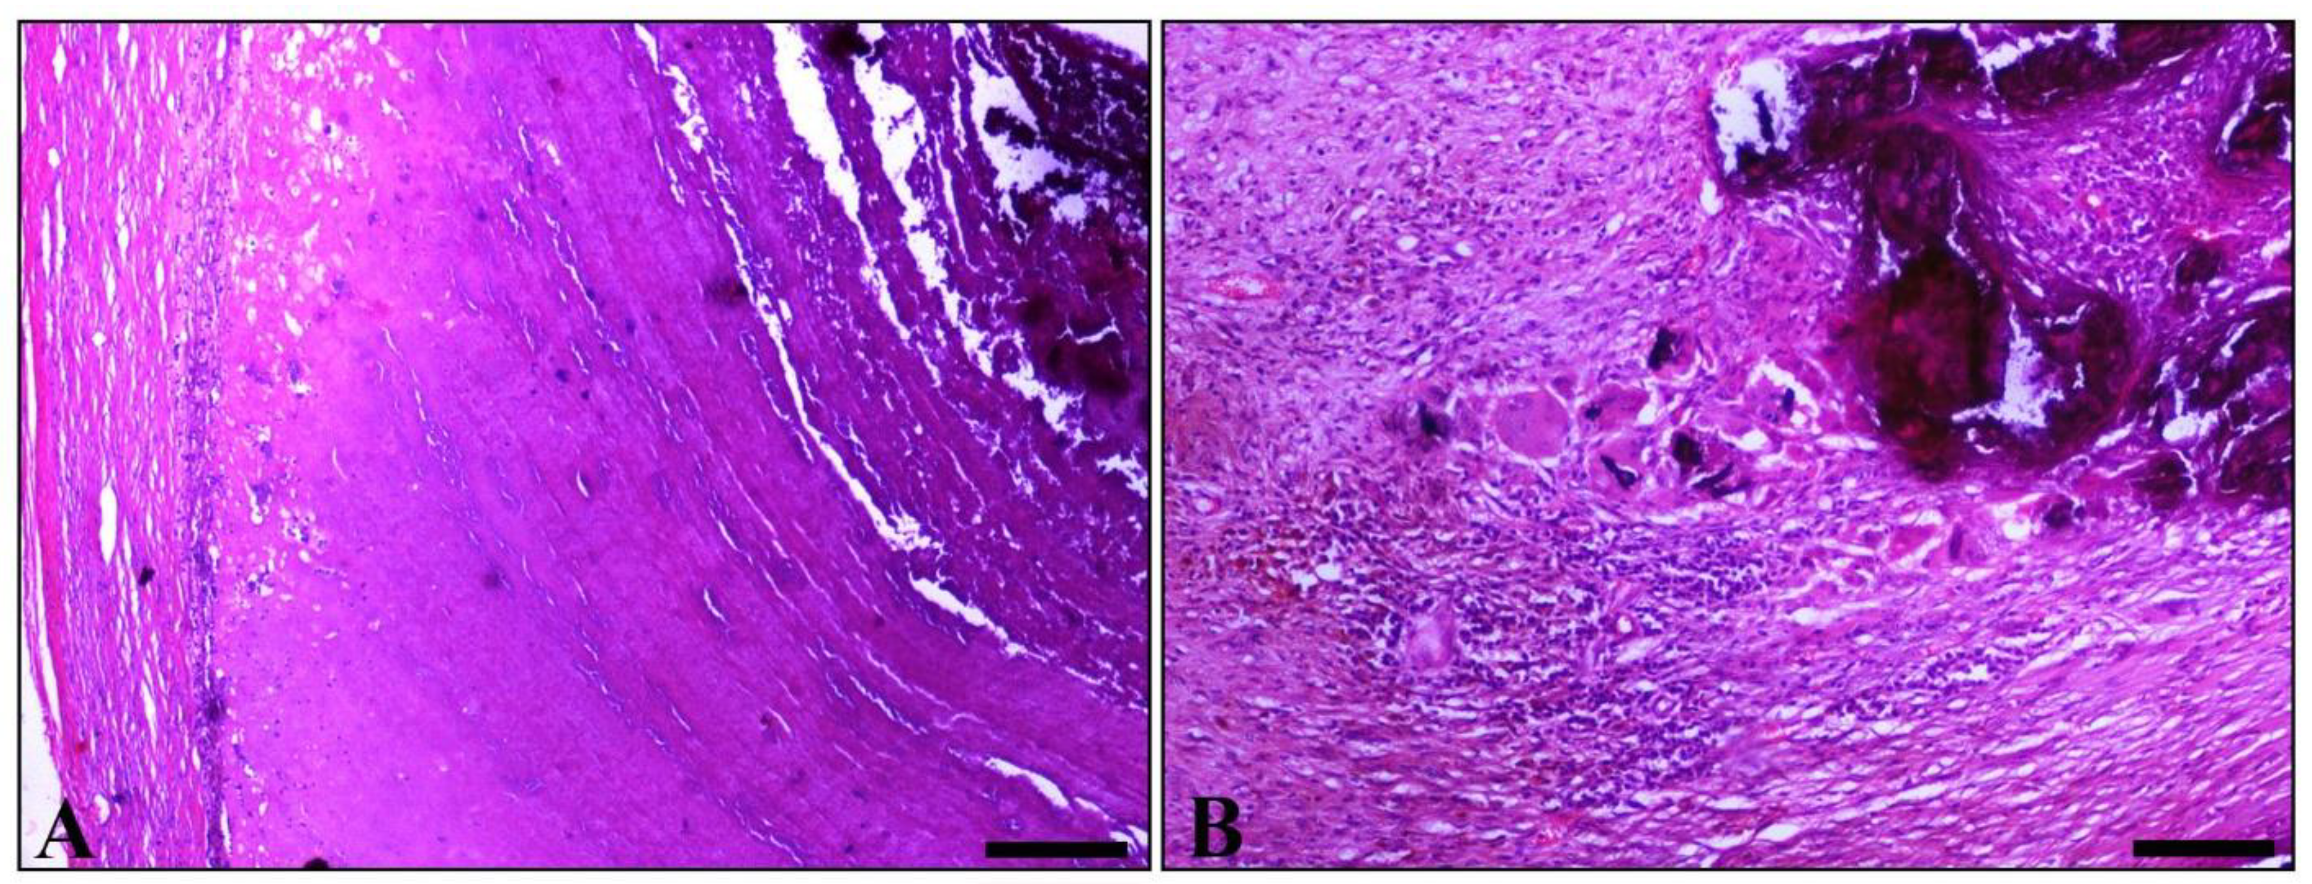

Varicocele in an Adult Ram: Histopathological Examination and Sperm Quality Evaluation

2. Case Presentation